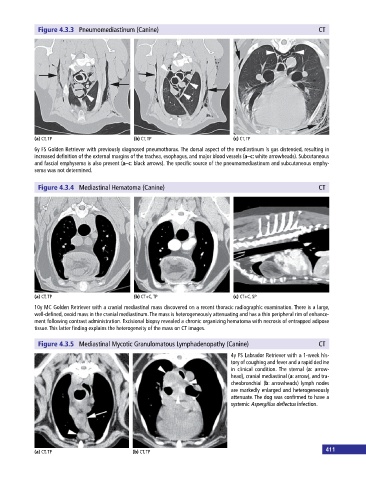

Figure 4.3.3 Pneumomediastinum (Canine) CT

(a) CT, TP (b) CT, TP (c) CT, TP

6y FS Golden Retriever with previously diagnosed pneumothorax. The dorsal aspect of the mediastinum is gas distended, resulting in

increased definition of the external margins of the trachea, esophagus, and major blood vessels (a–c: white arrowheads). Subcutaneous

and fascial emphysema is also present (a–c: black arrows). The specific source of the pneumomediastinum and subcutaneous emphy

sema was not determined.

Figure 4.3.4 Mediastinal Hematoma (Canine) CT

(a) CT, TP (b) CT+C, TP (c) CT+C, SP

10y MC Golden Retriever with a cranial mediastinal mass discovered on a recent thoracic radiographic examination. There is a large,

well‐defined, ovoid mass in the cranial mediastinum. The mass is heterogeneously attenuating and has a thin peripheral rim of enhance

ment following contrast administration. Excisional biopsy revealed a chronic organizing hematoma with necrosis of entrapped adipose

tissue. This latter finding explains the heterogeneity of the mass on CT images.

Figure 4.3.5 Mediastinal Mycotic Granulomatous Lymphadenopathy (Canine) CT

4y FS Labrador Retriever with a 1‐week his

tory of coughing and fever and a rapid decline

in clinical condition. The sternal (a: arrow

head), cranial mediastinal (a: arrow), and tra

cheobronchial (b: arrowheads) lymph nodes

are markedly enlarged and heterogeneously

attenuate. The dog was confirmed to have a

systemic Aspergillus deflectus infection.

(a) CT, TP (b) CT, TP